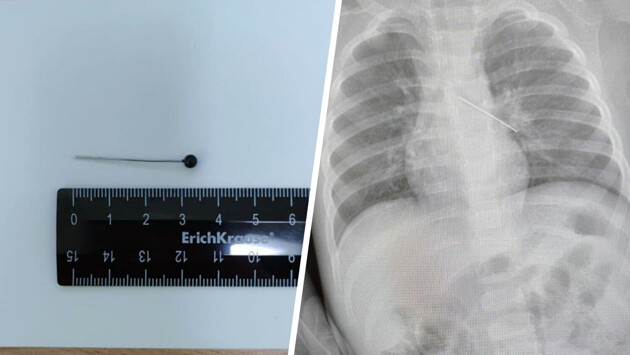

По словам медика, мать мальчика вовремя заметила беду и привезла ребенка в медицинское учреждение. Обследование показало, что инородный предмет зафиксировался в бронхах.

«Если бы бригада наших высокопрофессиональных специалистов не смогла удалить инородный предмет с помощью бронхоскопа, ребенка пришлось бы передавать торакальным хирургам для проведения большой операции», — пояснила Белоцерковцева.